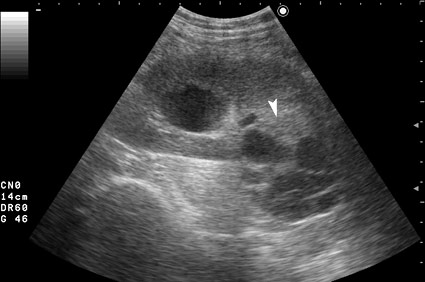

Профилактический осмотр, жалоб не предъявляет.

Серошкальное УЗИ. В области нижнего полюса определяется образование сложной структуры (стрелка).

Да, это был рак почки, кистозная форма. Гистология - светлоклеточный рак.